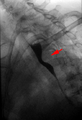

Aberrant subclavian artery seen at swallowing study: Impression of the esophagus from behind.